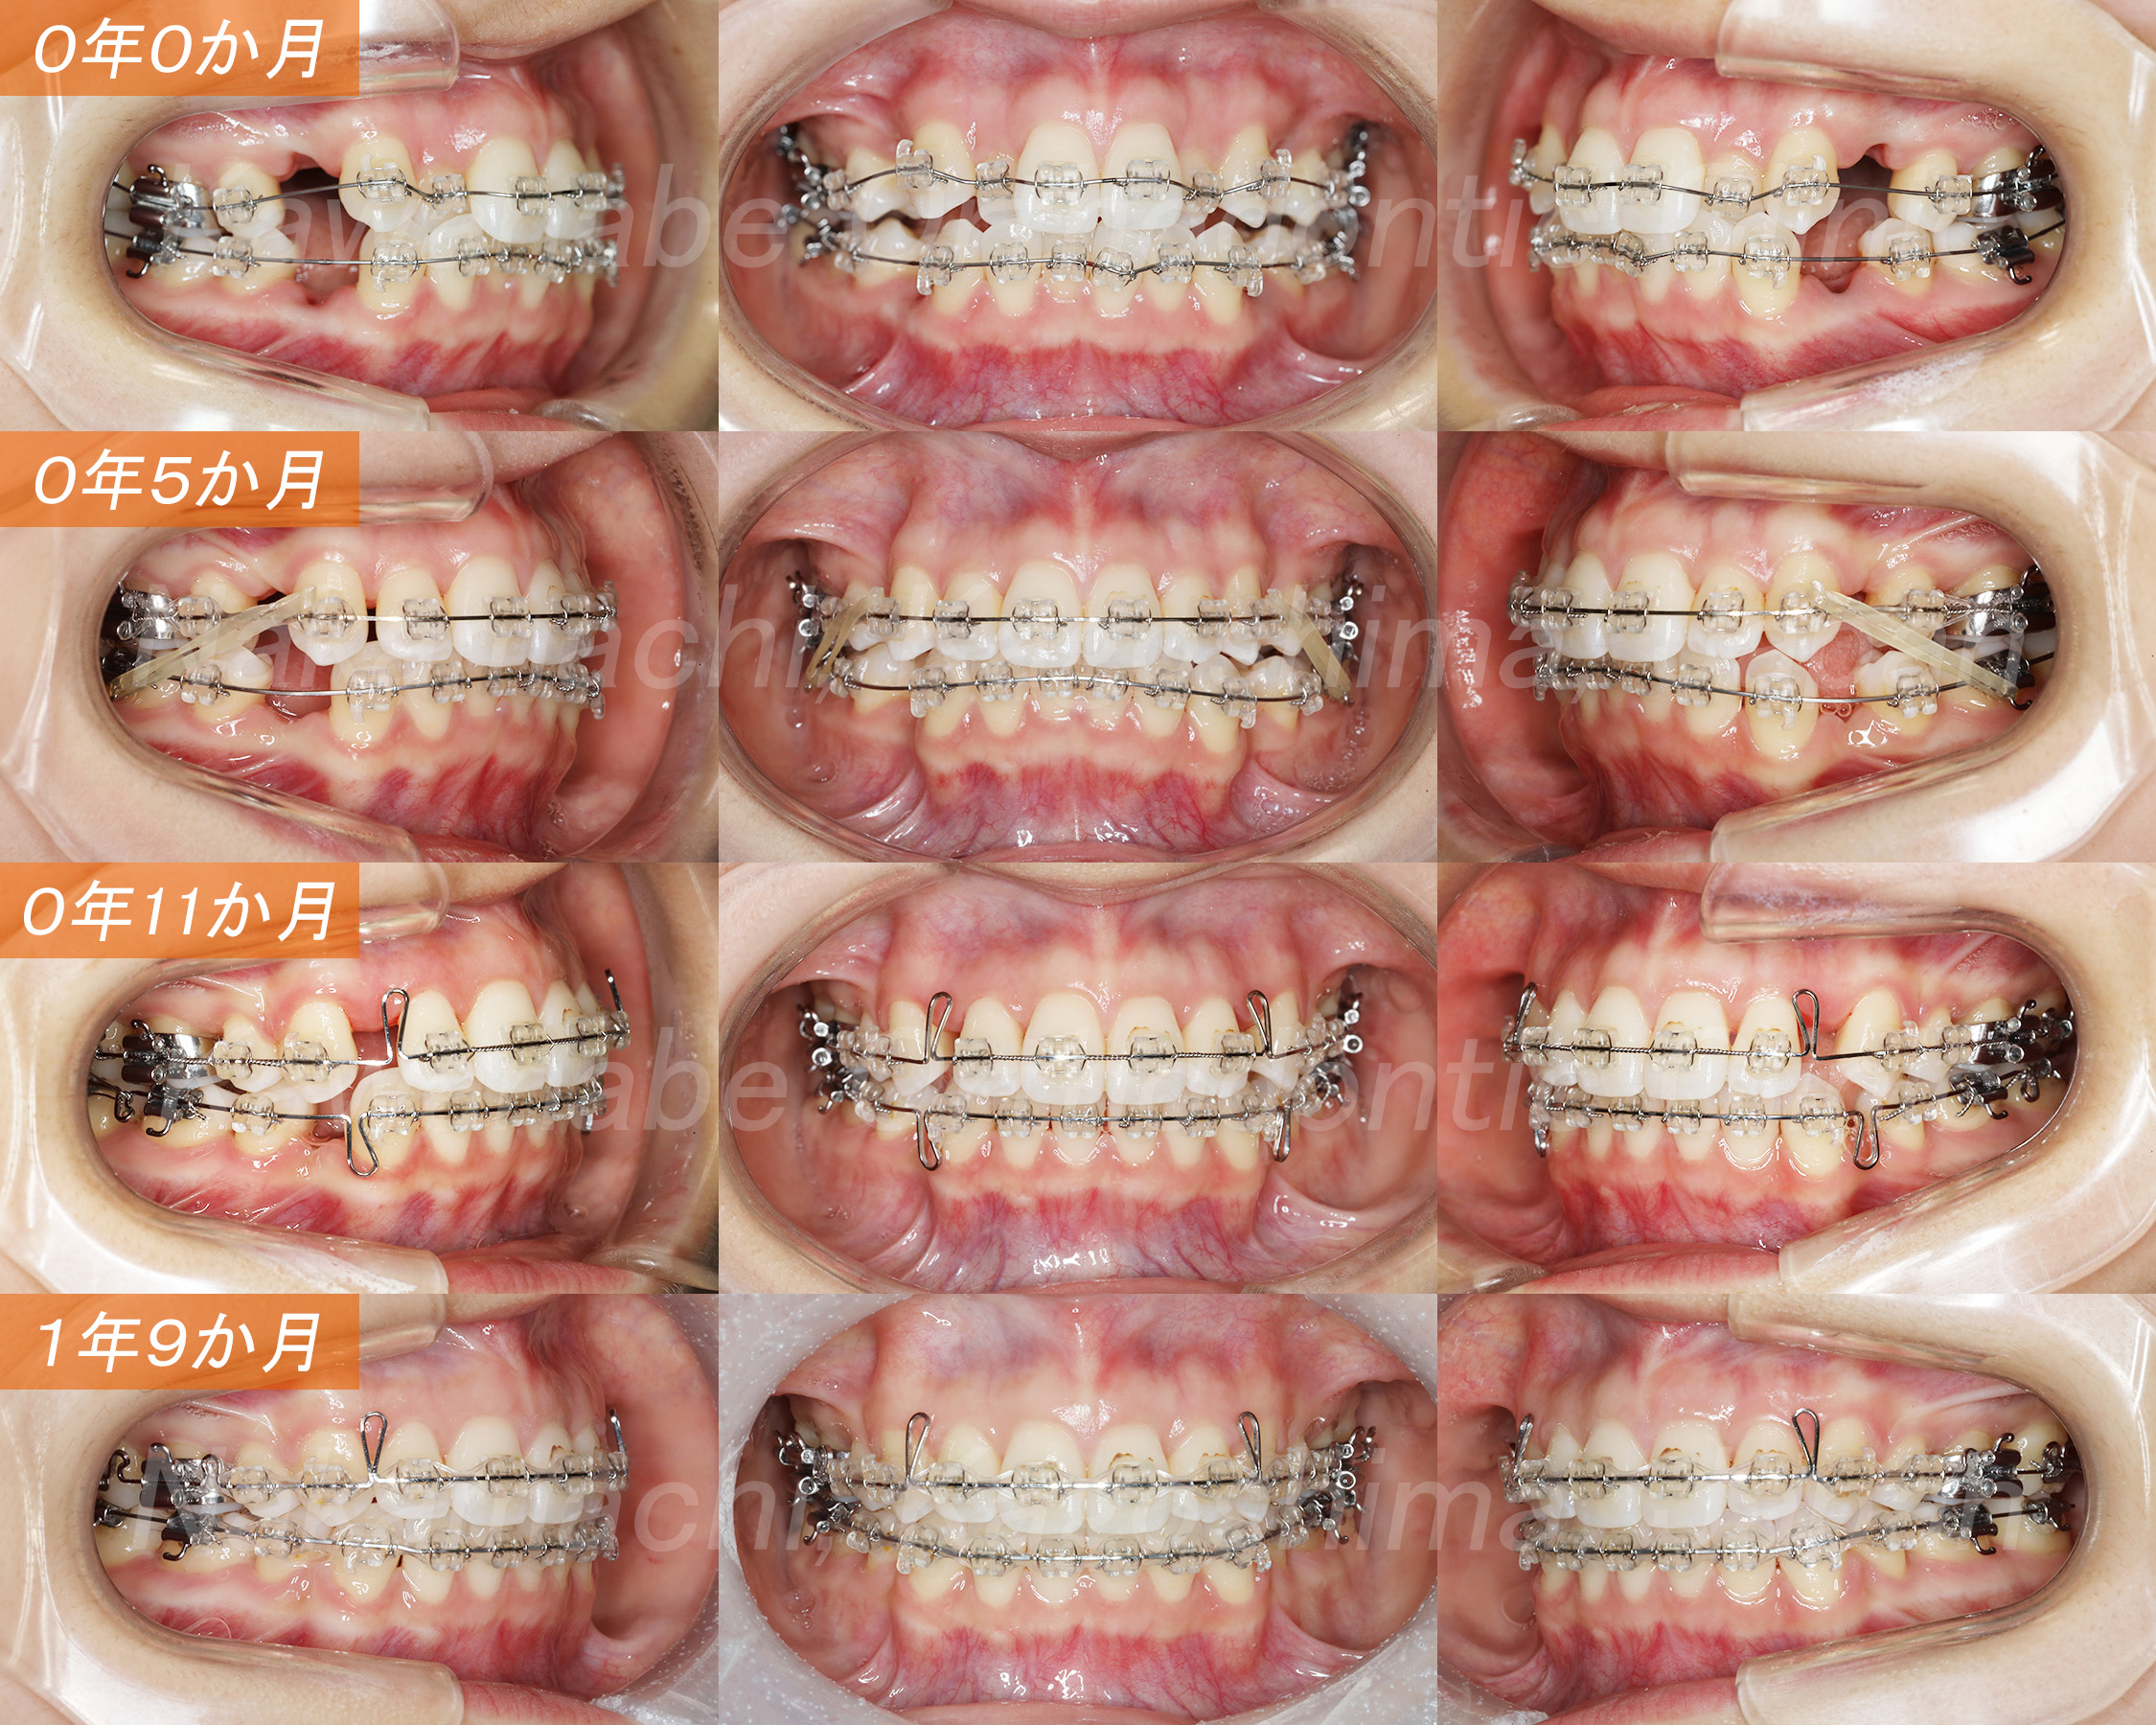

0年0か月:レベリング

0年5か月:上顎犬歯牽引

0年11か月:上下顎前歯牽引

1年9か月:ディテイリング

マルチブラケット装置を用いた叢生の治療です。歯科矯正用アンカースクリューは使用せず、代わりにヘッドギアとII級ゴムを用いて治療を行いました。治療後は叢生だけでなく口唇突出も改善されて、とても素敵な笑顔になりました。